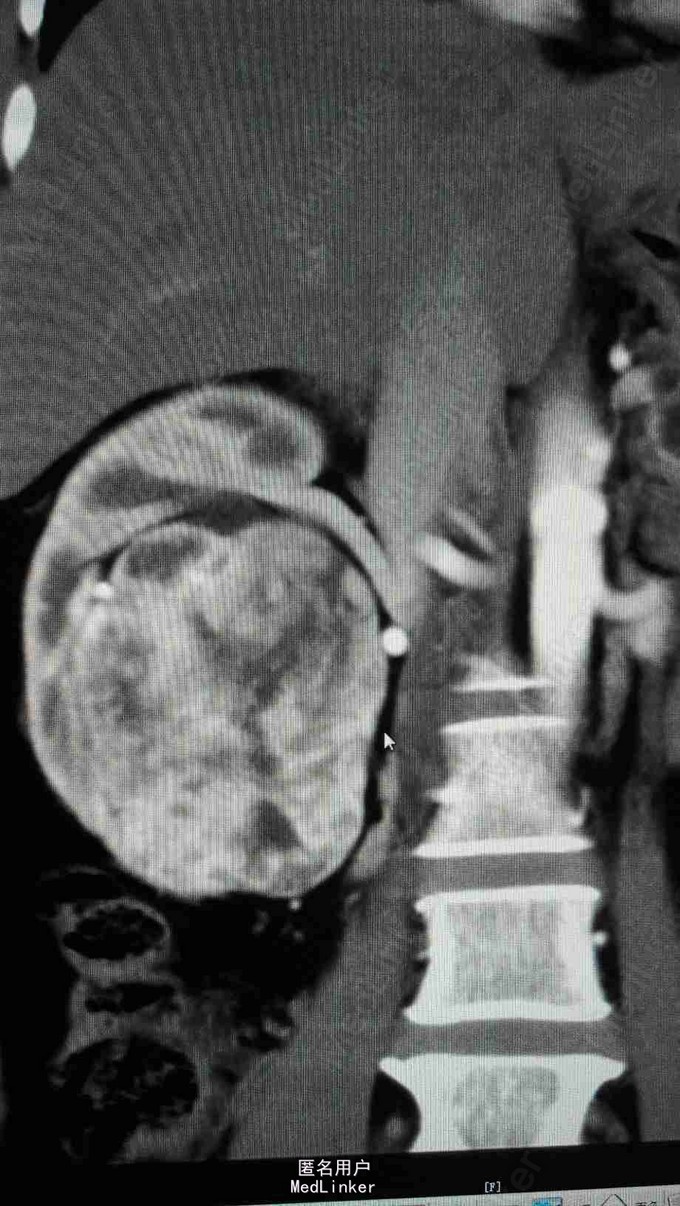

查体:T 36.5℃,P 81bpm,R 18bpm,BP 127/79mmHg;心肺腹及神经查体未及明显异常。 检查:三大常规、生化、凝血、乙肝、丙肝、梅毒、HIV未见明显异常。 头颅MRA:小脑蚓部占位,血管母细胞溜可能性大;左椎动脉颅内段局部轻度狭窄;左侧大脑前动脉A1段稍细。 腹部超声:右肾混合性占位性病变(中下极见一个大小约90*65*83mm的混合回声团,边界尚清,内回声不均,可见密集分布的无回声囊,呈蜂窝状);右肾局限性积液;胰腺内异常回声(多个大小不等的无回声囊,大者约12*11mm,边界清);双侧卵巢小囊(27*25mm(右)、25*25mm(左));肝、胆、脾未见明显异常;左肾、膀胱未见明显异常;双侧输尿管未见明显扩张;子宫未见明显异常。腹部增强CT ,胰腺多发囊性病变,右肾巨大占位,考虑肾癌。